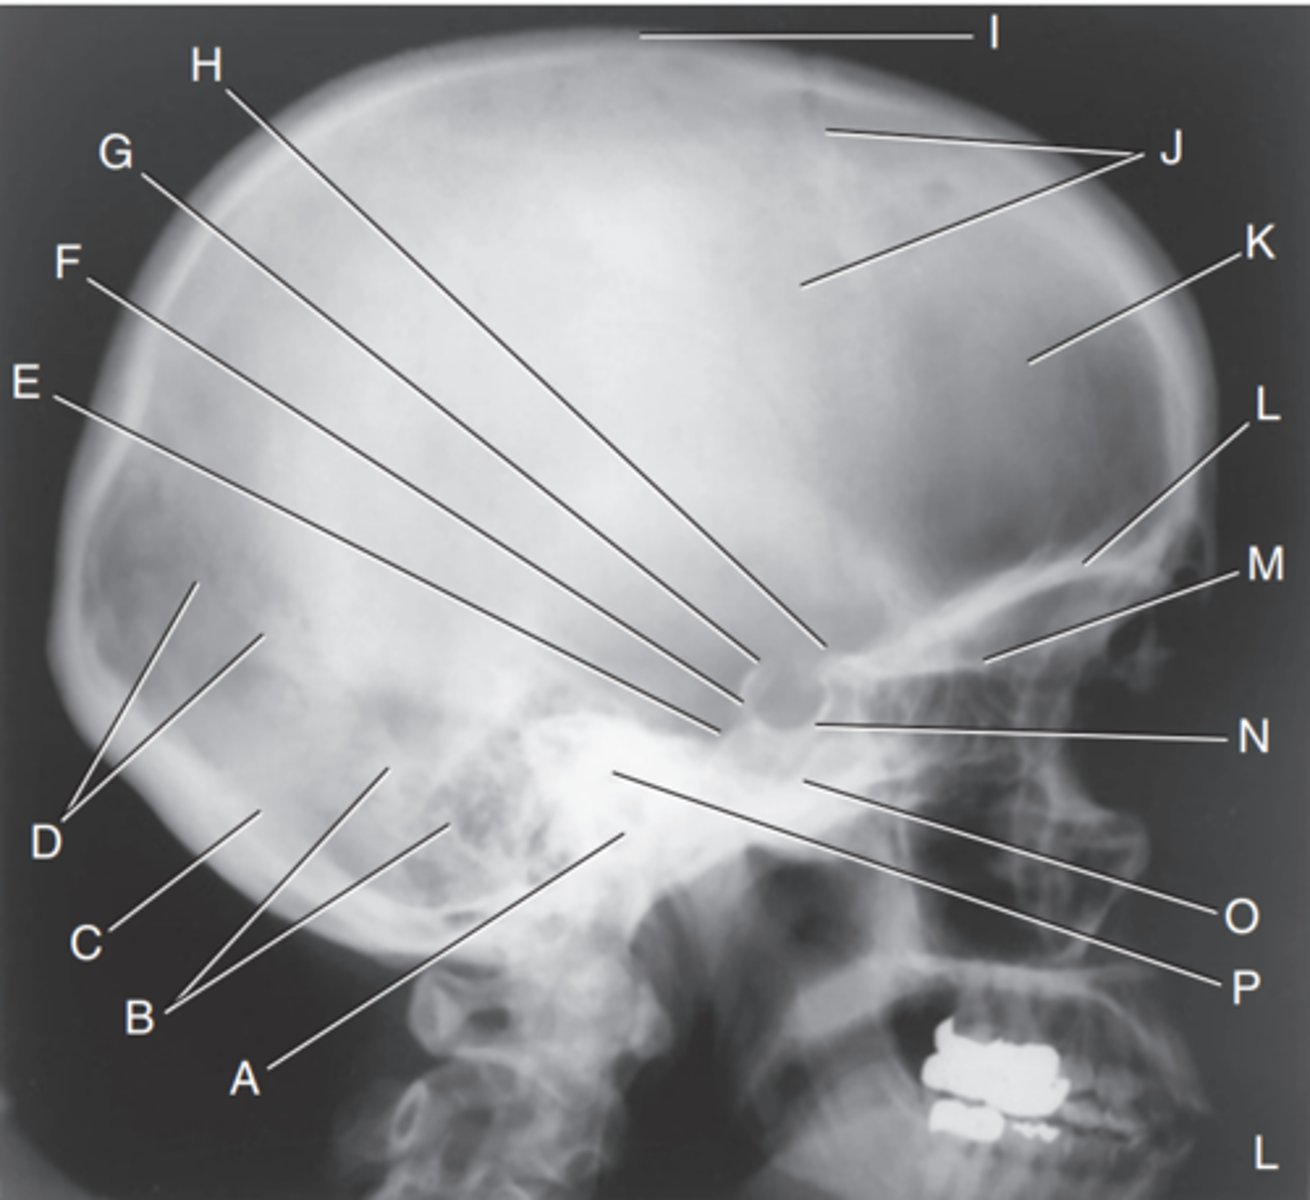

EAM

Label A

Mastoid portion of temporal bone

Label B

Occipital bone

Label C

Lambdoidal suture

Label D

Clivus

Label E

Dorsum sellae

Label F

Posterior clinoid processes

Label G

Anterior clinoid processes

Label H

Vertex of cranium

Label I

Coronal suture

Label J

Frontal bone

Label K

Orbital plates

label L

Cribriform plate

Label M

Sella turcica

Label N

Body of sphenoid (sphenoid sinus)

Label O

Petrous portion of temporal bone

Label P